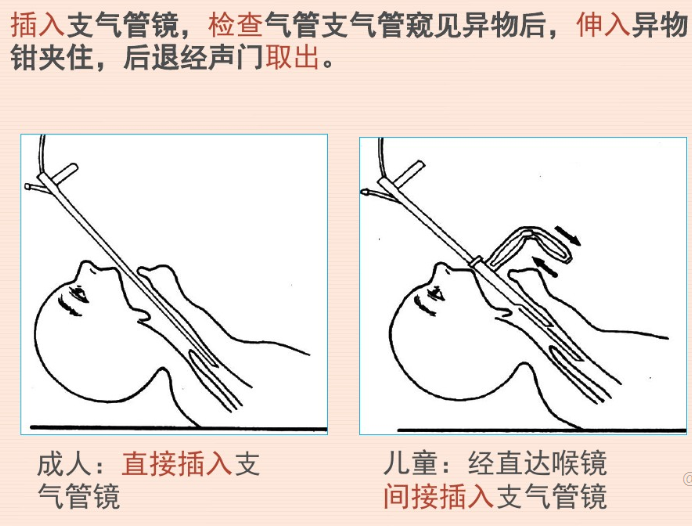

考虑到呛入气管内的白虾体积较大,无法经鼻腔取出,我们为该患者进行了经口气管镜检查。

主要指外源性物体经口或鼻误吸入声门,停留于气管、支气管内而致病者。